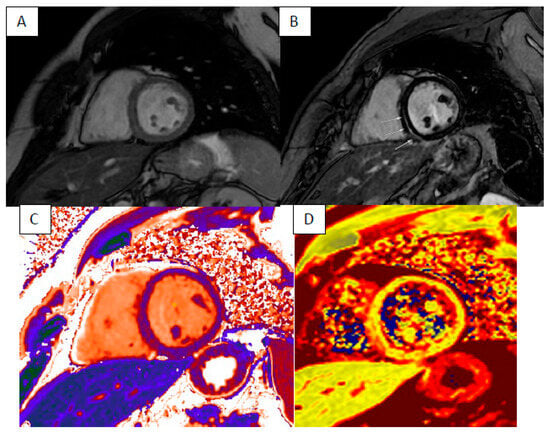

4. Cardiac Amyloidosis